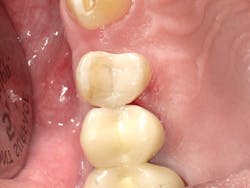

In Case Two, we'll replace an old composite inlay (figure 6). As in the first case, the LiteTouch erbium YAG laser was used to remove the inlay without anesthetic. As the decay had spread subgingivally on the interproximal surface, a small gingivectomy was needed to access the final gingival margin. After placing some topical anesthetic on the soft tissue and using a low energy setting, the Lite Touch laser was used to remove the excess interproximal soft tissue (figure 7). A sectional matrix band and newly designed Fusion Wedge (Garrison) was placed, and the band lightly burnished against the adjacent tooth (figure 8). A self-etch adhesive technique using Futurabond U was used. After curing the adhesive, a bulk-fill flowable (x-tra base, Voco) was used in the floor of the box. Using a flowable bulk fill in this fashion virtually assures you of a tight gingival seal at the bottom of the proximal box. Next, Admira Fusion Opaque shade OA3 was used to mimic the dentin (figure 9), followed by placement of the final enamel layer of material. The finished restoration exhibits a high polish with a close-up intraoral appearance that mimics a ceramic inlay (figure 10).

Figure 6

Figure 7

Figure 8

Figure 9

Figure 10